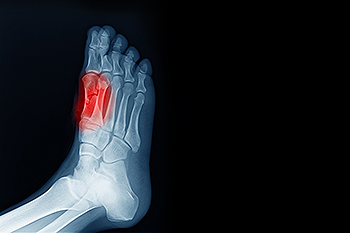

Three Conditions That Affect the Big Toe Joint

The big toe joint, known as the first metatarsophalangeal, or MTP, joint, connects the toe bones to the foot and supports body weight with each step. Because of this constant stress, it is vulnerable to several conditions. Bunions may develop when the big toe shifts toward the second toe, often causing pain and deformity. Turf toe occurs when the big toe is forced upward, straining ligaments and tissues surrounding the joint. Osteoarthritis may result from long-term wear and tear, while inflammatory arthritis can cause stiffness, swelling, and deformities. Additionally, gout may strike suddenly, producing severe pain, redness, and swelling when uric acid crystals collect within the joint. Infections, including septic arthritis, can also lead to rapid big toe joint damage and require prompt care. A podiatrist can provide treatment options including wearing supportive footwear, and even surgery, in serious cases. If you have ongoing pain in the big toe joint, it is suggested that you schedule an appointment with a podiatrist for an exam and appropriate treatment.

Types of Broken Toes

Broken toes can range from simple cracks in the bone to more severe fractures that involve joint displacement or multiple bone fragments. These injuries often result from sudden trauma, such as dropping a heavy object on the foot or forcefully striking a hard surface. Common symptoms include sharp pain, swelling, bruising, and difficulty walking, especially if pressure on the affected toe causes discomfort. A toe that appears crooked or shortened compared to its neighbors may indicate a displaced fracture or dislocation. A podiatrist will typically perform a thorough foot exam and may use X-rays to confirm the type and severity of the fracture. If the bone is misaligned or severely broken, surgery may be needed to restore proper toe position and prevent long-term complications. If you have broken a toe, it is suggested that you make an appointment with a podiatrist for an exam and suggested treatment options.